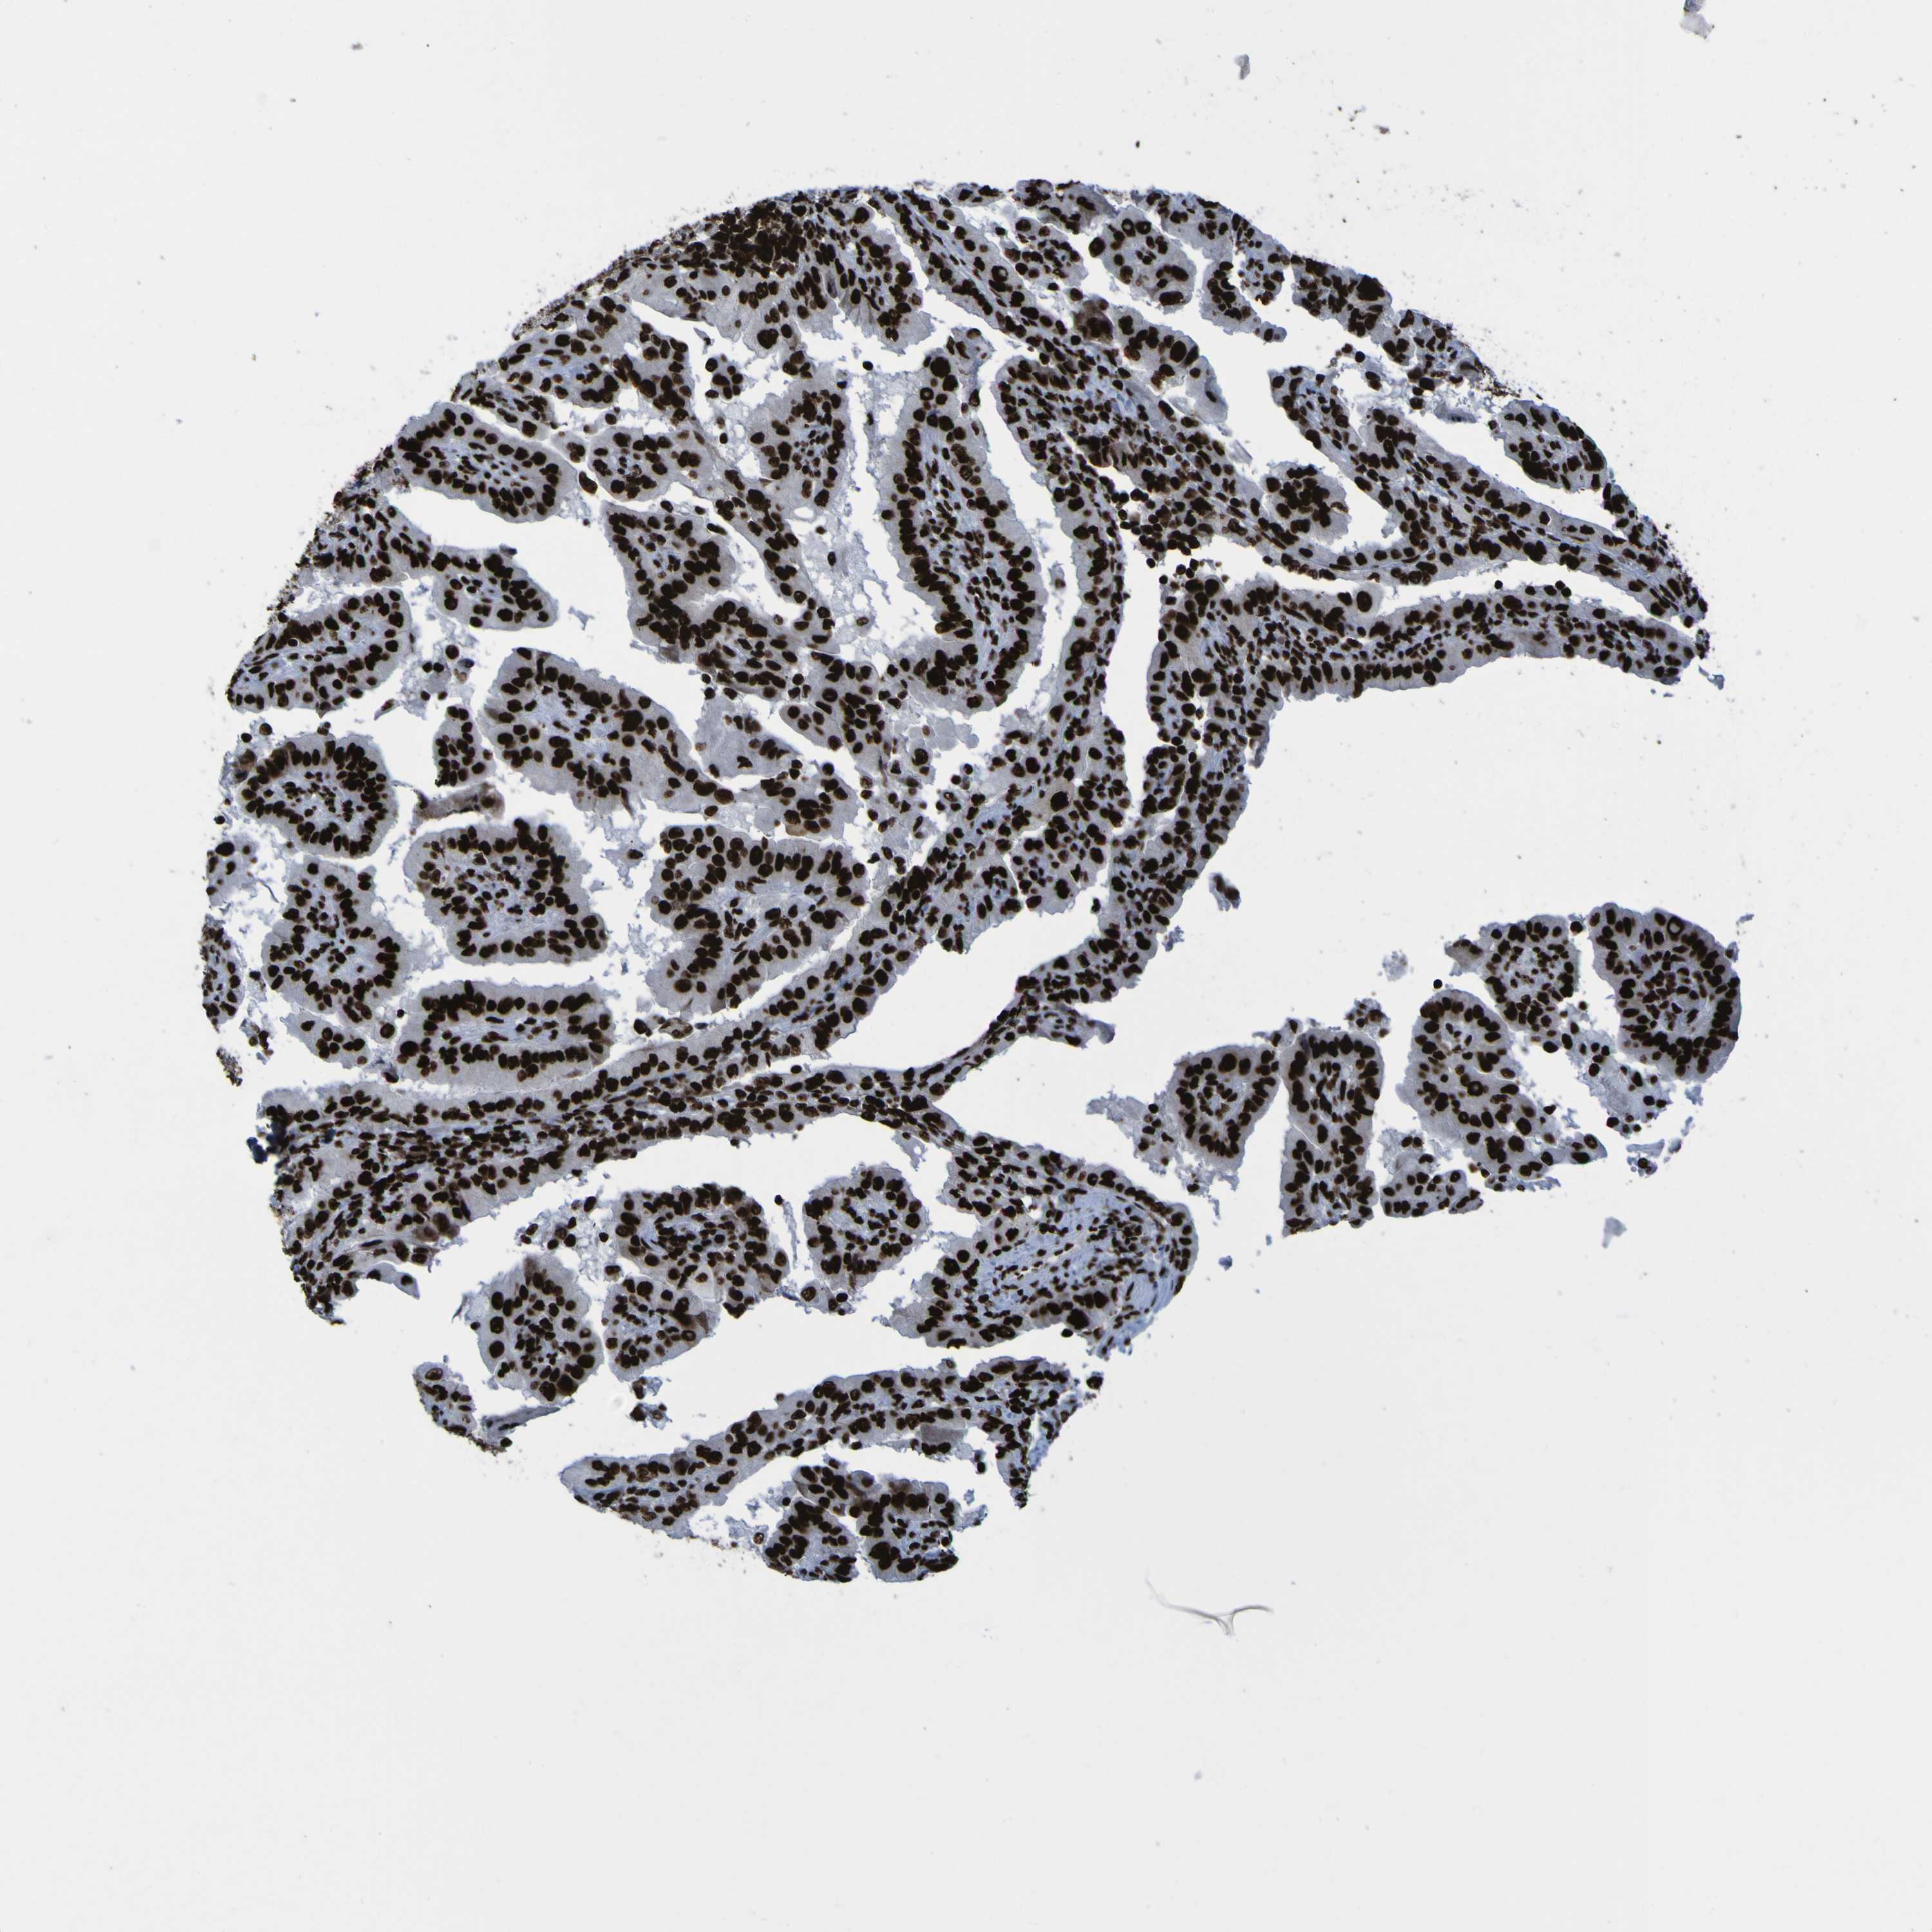

THYROID CANCER - Protein expressioni

A mouse-over function shows sample information and annotation data. Click on an image to view it in a full screen mode. Samples can be filtered based on level of antibody staining by selecting one or several of the following categories: high, medium, low and not detected. The assay and annotation is described here.

Note that samples used for immunohistochemistry by the Human Protein Atlas do not correspond to samples in the TCGA dataset.

Antibody stainingi

Antibody staining in the annotated cell types in the current human tissue is reported as not detected, low, medium, or high, based on conventional immunohistochemistry profiling in selected tissues. This score is based on the combination of the staining intensity and fraction of stained cells.

Each image is clickable and will lead to virtual microscopy that enables deeper exploration of all samples and also displays staining intensity scores, fraction scores and subcellular localization as well as patient and tissue information for each sample.

Antibody HPA011384

Antibody CAB012983

Staining

High

Medium

Low

Not detected

Intensity

Strong

Moderate

Weak

Negative

Quantity

>75%

75%-25%

<25%

None

Location

Nuclear

Cytoplasmic/membranous

Cytoplasmic/membranous,nuclear

Papillary adenocarcinoma, NOS

Follicular adenoma carcinoma, NOS